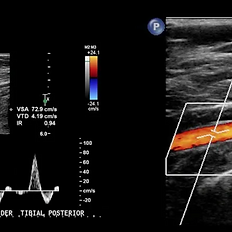

Doppler ultrasound of the upper or lower limbs is a non-invasive vascular study that analyzes blood flow in the arteries of the arms and legs using high-resolution ultrasound combined with color and spectral Doppler technology. This examination allows for the assessment of patency, flow velocity, and the presence of arterial narrowing or obstructions (stenosis or occlusions), providing a comprehensive view of the peripheral circulation. During the procedure, the main arteries of the upper limb (subclavian, axillary, brachial, radial, and ulnar) or lower limb (common femoral, superficial femoral, popliteal, tibial, and peroneal) are examined, evaluating flow quality, the presence of atherosclerotic plaques, and distal perfusion. Most frequent clinical indications: Leg or arm pain during exertion (intermittent claudication). Coldness, tingling, or discoloration of the extremities. Wounds or ulcers that do not heal. Suspected peripheral arterial disease (PAD) or thoracic outlet syndrome. Follow-up after vascular bypass, angioplasty, or stent placement. Monitoring in patients with diabetes, hypertension, smoking, or dyslipidemia. The exam is painless, safe, and radiation-free, providing detailed hemodynamic information about arterial function. The results allow for the identification of circulatory abnormalities before serious complications such as ischemia, ulcers, or amputations occur. Preparation: Fasting is not required. Comfortable clothing that allows for exposure of upper or lower limbs is recommended. 馃搷 Schedule your arterial Doppler study and evaluate the health of your circulatory system with advanced ultrasound technology.